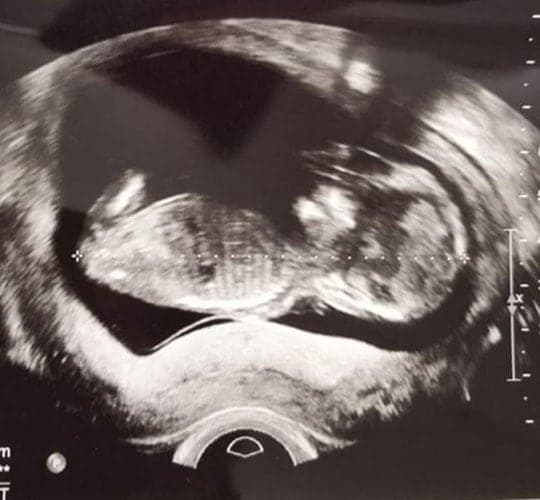

Ultraschallbilder aus dem 1. Trimester (1. SSW bis 12. SSW)

Im ersten Trimester sind die Ultraschallbilder meist noch schwer zu deuten. Oft erkennt man in den letzen Wochen des ersten Trimesters gut den Körper, den Kopf und die Gliedmaße. Das Geschlecht kann man in dieser Zeit meist noch nicht erkennen.